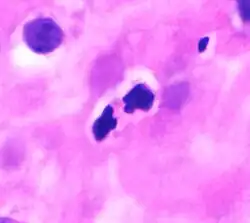

These cells are eosinophilic or "acid-loving" due to their large acidophilic cytoplasmic granules, which show their affinity for acids by their affinity to coal tar dyes: Normally transparent, it is this affinity that causes them to appear brick-red after staining with eosin, a red dye, using the Romanowsky method.[4] The staining is concentrated in small granules within the cellular cytoplasm, which contain many chemical mediators, such as eosinophil peroxidase, ribonuclease (RNase), deoxyribonucleases (DNase), lipase, plasminogen, and major basic protein. These mediators are released by a process called degranulation following activation of the eosinophil, and are toxic to both parasite and host tissues.

In normal individuals, eosinophils make up about 1–3% of white blood cells, and are about 12–17 micrometres in size with bilobed nuclei.[3][5] While eosinophils are released into the bloodstream, they reside in tissue.[4] They are found in the medulla and the junction between the cortex and medulla of the thymus, and, in the lower gastrointestinal tract, ovaries, uterus, spleen, prostate, and lymph nodes, but not in the skin, lungs, esophagus, or some other internal organs under normal conditions. The presence of eosinophils in these latter organs is associated with disease. For instance, patients with eosinophilic asthma have high levels of eosinophils that lead to inflammation and tissue damage, making it more difficult for patients to breathe.[6][7] Eosinophils persist in the circulation for 8–12 hours, and can survive in tissue for an additional 8–12 days in the absence of stimulation.[8] Pioneering work in the 1980s elucidated that eosinophils were unique granulocytes, having the capacity to survive for extended periods of time after their maturation as demonstrated by ex-vivo culture experiments.[9]